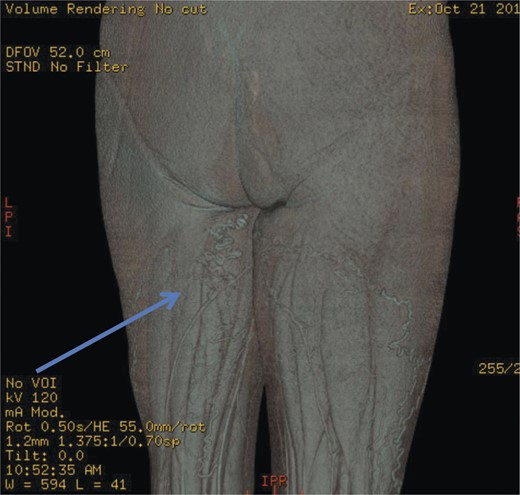

Initial investigations included duplex scan, followed by magnetic resonance scan. Duplex scanning demonstrated a competent sapheno-femoral (SFJ) and Sapheno-popliteal (SPJ) junctions bilaterally; however, did raise suspicion of a pelvic origin of the vulval varices with congested pelvic veins. Magnetic resonance venogram aided the diagnosis by demonstrating the communication of the vulval varices to the upper thigh veins with contribution from the internal iliac vein. In this case there was no evidence of ovarian varices (Fig. 1). Catheter venography was unable to confirm the contributing vein with certainty but computed pelvic venography showed a likely connection through the superficial external pudendal vein (Fig. 2).

Computed pelvic venography showing communication of thigh veins to vulval varices (blue arrow).